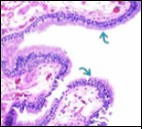

Figure 2.Ciliated cutaneous cyst with an undulating layer of ciliated cuboidal epithelium and supporting fibrous tissue framework (12).

Typically, cutaneous ciliated cyst is a simple cyst which demonstrates a layering of pseudostratified ciliated columnar epithelium recapitulating conventional epithelial lining of the fallopian tube. As the cutaneous ciliated cyst demonstrates a morphological similarity to the fallopian tube lining epithelium, a Mullerian origin is indicated. Gross examination of cutaneous ciliated cyst depicts a solitary, mobile, non-tender, fluctuant, firm or soft to cystic lump with a fibrous wall and abundant amount of circumscribing adipose tissue. Cutaneous ciliated cysts are of a variable dimension. Cut surface usually displays a unilocular cyst impacted with clear, serous fluid, an attenuated smooth, greyish/ white cyst wall incorporated with incomplete septa traversing the cyst 6, 7.

Cystic structures cogitated within deep dermal or subcutaneous tissue can be impacted with haemorrhagic fluid. Cyst lining is smooth, regular and is essentially composed of a singular layer of columnar epithelium with focally pseudostratified columnar epithelium, a circumscription of loosely configured, well vascularized, fibroconnective or fibrocollagenous tissue and an absence of inflammatory infiltrate.